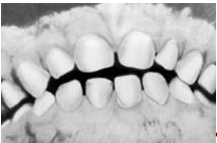

Кроме аномалий П. в сагиттальной плоскости существуют аномалии П. в вертикальной и трансверзальной плоскостях. К основным вертикальным аномалиям (определяются по отношению к горизонтальной плоскости) относится открытый и глубокий П. Открытый П. (рис. 7, а) — наличие щели между зубными рядами при их смыкании, чаще в области передних зубов, реже в области боковых. Иногда смыкаются только последние моляры, что приводит к выраженным нарушениям жевательной функции и особенно речи. При глубоком П. (рис. 7, б) передние зубы одной из челюстей в значительной степени перекрывают коронки зубов-антагонистов, нижние резцы не опираются на зубные бугорки верхних резцов, а соскальзывают к их десневому краю, что приводит к постоянному травмированию десен и неба; нижняя часть лица укорочена за счет уменьшения или дистального положения подбородка.

К трансверзальным аномалиям, определяемым по отношению к сагиттальной плоскости, относится перекрестный П. (рис. 7, в), при котором верхний зубной ряд в области боковых участков в значительной степени перекрывает нижний зубной ряд (латерогнатический П.) или нижний перекрывает верхний (латерогенический П.).

Рис. 7а). Схематическое изображение челюстей при открытом прикусе.

Рис. 7б). Схематическое изображение челюстей при глубоком прикусе.

Рис. 7в). Схематическое изображение челюстей при перекрестном прикусе.